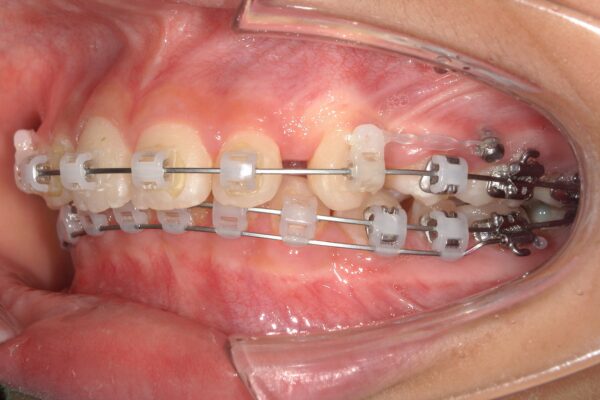

①装置装着~4か月後:咬み合わせの土台作り

まずは犬歯を後ろへ移動させるとともに、深い咬み合わせ(過蓋咬合)を改善するため、下顎にワイヤーを2本用いる手法で、前歯を押し下げて咬み合わせを浅くすることで咬合挙上(こうごうきょじょう)を図りました。

②装置装着8か月後:レジンマウントによる挙上

さらに下顎の奥歯に「レジンマウント(プラスチックの盛り物)」を装着し、咬み合わせの高さ(咬合高径)を強制的に確保しました。これにより、歯が動く際の邪魔な干渉を取り除きます。